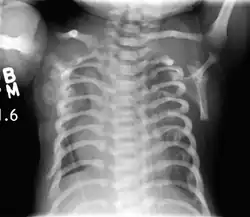

Lateral CXR of the same person above

Jeune syndrome is a rare genetic disorder that affects the way a child's cartilage and bones develop. It begins before the child is born and primarily affects the child's rib cage, pelvis, arms and legs.[5] Usually, problems with the rib cage cause the most serious health problems for children with Jeune syndrome. Their rib cages (thorax) are smaller and narrower than usual, which inhibits the child's lungs from developing fully or expanding when they inhale. The child may breathe rapidly and shallowly. They may have trouble breathing when they have an upper or lower respiratory infection, like pneumonia. Breathing trouble can range from mild to severe. In some children, it is not noticeable, aside from fast breathing; however, in others, breathing problems can be fatal. About 60% to 70% of children with this condition die from respiratory failure as babies or young children. Children with Jeune syndrome who survive often develop problems with their kidneys, and over time they may experience kidney failure.[2] As a result, few children with Jeune syndrome live into their teen years. Children with Jeune syndrome have a form of dwarfism. They are short in stature, and their arms and legs are shorter than most people's.[6]